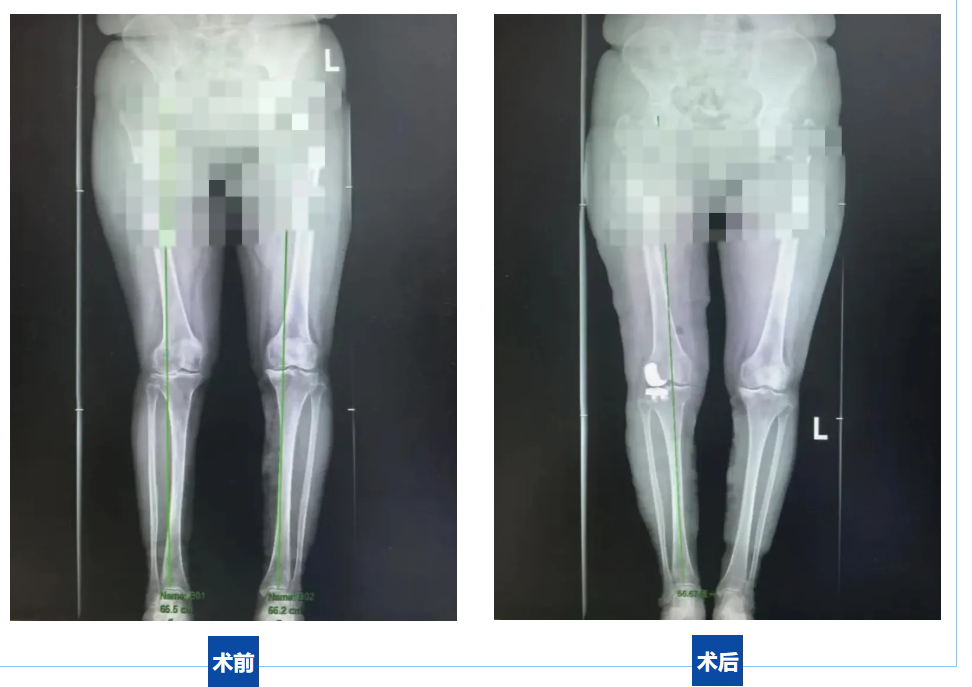

在尝试多种保守治疗均无效后,患者慕名来到延安市中医医院运动医学科就诊。经三维CT、生物力学评估及X线检查(显示外侧间隙消失、股骨髁严重磨损),患者被明确诊断为外侧间室重度骨关节炎合并固定外翻畸形。

“手术当晚就能站着刷牙,我以为在做梦!”患者感慨地说道,“现在每天散步30分钟,膝盖不再‘卡住’了,能自己买菜、逛公园,这才是退休该有的生活!”术后1个月随访,患者膝关节外翻畸形矫正,HSS评分从术前的52分提升至89分,实现了“从寸步难行到自由行走”的跨越。